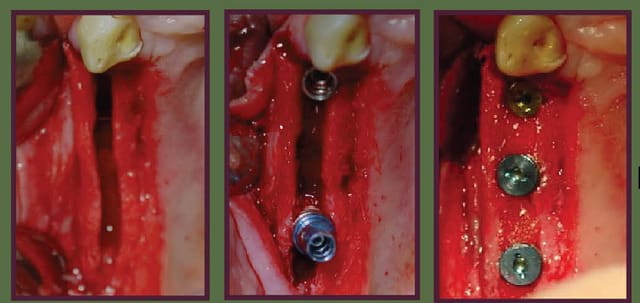

c'est tout chaud de ce début d'après-midi

très bonne stabilité primaire dans la zone greffée.

Au départ la 13 devait être gardée mais suite à un accident la racine s'est fracturée donc extraction et pose d'un implant. J'ai fait une ROG (granules biobank et membrane collagène) et arrondis l'angle distal du greffon.

Pas d'autres photos que celle-ci car timing cabinet très serré en ce moment. Mais en gros: implant en 12 22 de 4 mm de diamètre et 12 de long au niveau des greffons et 2 de 10x4.5 en 13 23 avec ROG granules biobank + membranes, le tout bien empaqueté.